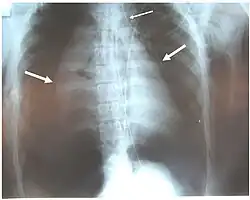

A radiografia de tórax é a técnica inicial de imagem usada para diagnosticar a lesão traqueobrônquica.[17] A imagem pode não mostrar sinais em pacientes assintomáticos.[15] Indicações de lesão traqueobrônquica em radiografias incluem deformidade na traqueia ou defeito na parede traqueal.[17] Radiografias também podem mostrar enfisema cervical, ar nos tecidos do pescoço.[2] Raios X podem revelar lesões associadas e sinais como fraturas e enfisema subcutâneo.[2] Se o enfisema subcutâneo ocorre e o osso hioide aparece em uma radiografia posicionado anormalmente alto na garganta, pode indicar que a traqueia foi seccionada.[4] A lesão traqueobrônquica também é suspeita se um tubo traqueal aparece deslocado em uma radiografia, ou se seu balonete parece mais cheio que o normal ou protrai através de um rasgo na via aérea.[17] Se um brônquio é completamente rasgado, o pulmão pode colapsar para fora, em direção à parede torácica (em vez de para dentro, como no pneumotórax usual), pois perde a fixação ao brônquio que o mantém centralizado.[6] Em uma pessoa deitada de costas, o pulmão colapsa em direção ao diafragma e às costas.[23] Esse sinal, descrito em 1969, chamado sinal do pulmão caído, é patognomônico [en] da lesão traqueobrônquica (diagnóstico exclusivo, pois não ocorre em outras condições); no entanto, é raro.[6] Em até um em cinco casos de trauma contuso com lesão traqueobrônquica, não há sinais na radiografia torácica.[23] A tomografia computadorizada detecta mais de 90% das lesões traqueobrônquicas por trauma contuso,[3] mas nem raios X nem tomografia substituem a broncoscopia.[6]